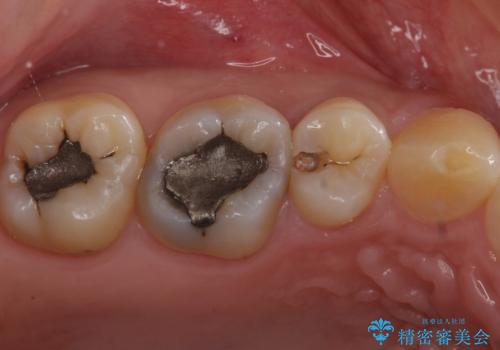

- 奥歯がしみるとのことで来院。

検査の結果、明らかに虫歯がある歯と修復物との間に虫歯がある歯が確認されました。

2歯とも白くて適合の良いセラミックインレーでの修復をすることとなりました。